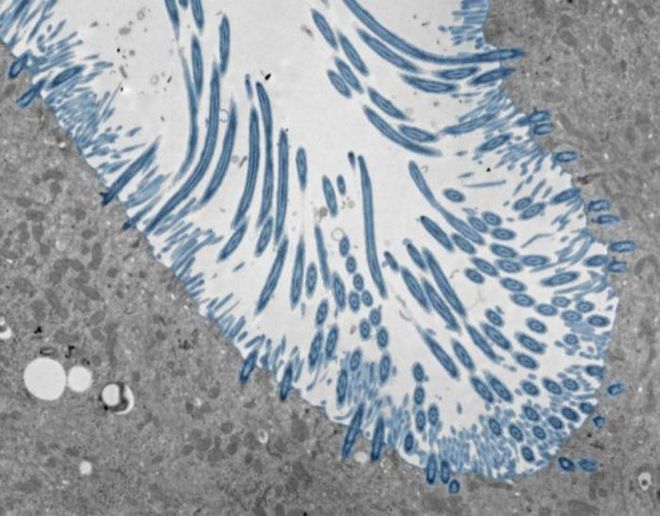

Image of a differentiated human nasal epithelial organoid with multiciliated cells in blue.

(Image Credit: Julien Amat & Bao Wang/CC BY-SA)